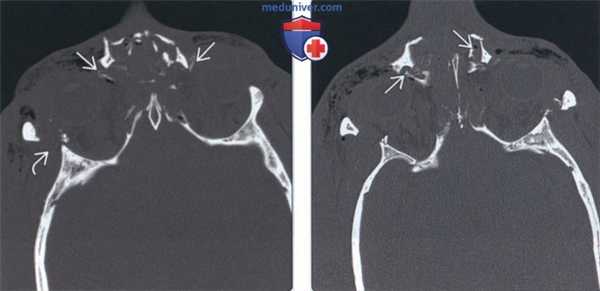

На аксиальных КТ-граммах признаками НОЭперелома являются: расхождение краев

назомаксиллярного шва, несимметричное

расположение носослезных каналов, затемнение и

разрушение решетчатых ячеек, депрессия и

смещение костей носа, перелом медиальной

стенки орбиты со смещением отломков, эмфизема

глазницы.

10. КТ-картина НОЭ-перелома:

КТ-картина

НОЭперелома:

а, б — телескопическое

смещение сломанных

костей носа назад, в

межорбитальное

пространство (стрелки).

в — прохождение линии

перелома через оба

носослезных канала

(длинные стрелки). г —

односторонний (геми-)

НОЭ-перелом

д — одностороннее расхождение назомаксиллярного шва на

аксиальной томограмме (длинная стрелка). Короткой стрелкой

отмечена зона диастаза скуловерхнечелюстного шва,

свидетельствующая о наличии у пострадавшего комбинации геми-НОЭи скулоорбитального переломов. е — аналогичное сочетание двух

переломов. Деструкция носослезного канала (длинная стрелка),

перелом скуловой дуги (короткая стрелка).